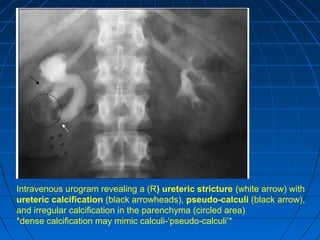

Intravenous urogram revealing a (R) ureteric stricture (white arrow) with

ureteric calcification (black arrowheads), pseudo-calculi (black arrow),

and irregular calcification in the parenchyma (circled area)

*dense calcification may mimic calculi ‘pseudo calculi’*‑ ‑